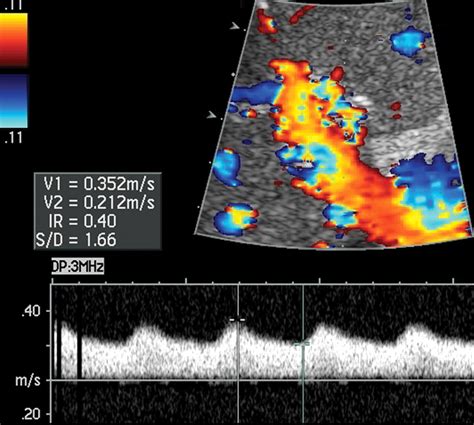

Because the Hepatic Artery Common is central to visceral perfusion, it is a primary area of concern in various medical scenarios, ranging from trauma to localized tumor management. When issues arise, such as an aneurysm, stenosis, or thrombosis, diagnostic imaging becomes the cornerstone of treatment planning. Physicians typically rely on advanced modalities to visualize this vessel clearly.

Doppler Ultrasound First-line assessment for blood flow velocity and direction.